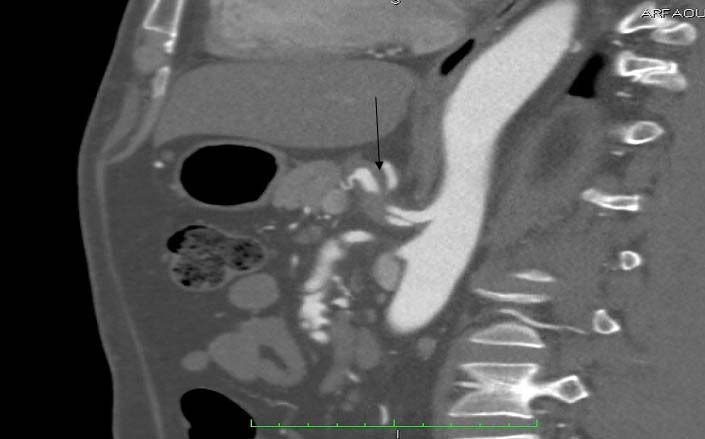

Laboratory data revealed leukocytosis with a white blood cell count of 11,000/ml. There was no evident pathology in the abdominal sonographic examination. An abdominal computed tomography scan with intravenous contrast showed a normal thoraco-abdominal aorta. However, dissection of both the celiac trunk and SMA was determined. SMA dissection was classified as Sakamoto type II b. There was no bowel oedema or free fluid. The dissection of the celiac artery was approximately 22mm long with aneurysmal dilatation [Table/Fig-1,2 and 3] with partial thrombosis causing moderate narrowing.

Abdominal CT scan with intravenous contrast (longitudinal view) reveals an isolated celiac artery dissection (arrow) measuring 22mm in length with aneurysmal dilatation.

Abdominal CT scan with IV contrast (Longitudinal view): demonstrates Celiac artery dissection.